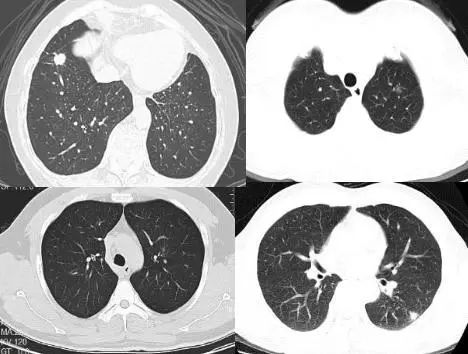

单个病灶定为孤立性,孤立性肺结节为边界清楚、密度增高、直径≤3 cm且周围被含气肺组织包绕的软组织影;2个以及以上的病灶定义为多发性,需要与转移性肺肿瘤鉴别诊断。

在2018年版的专家共识中,我们做了一个创新,首个共识提出大小分类:微小结节(直径<5mm),小结节(直径5-10 mm),肺结节(直径 30 mm以下)。这样分类有助于分级诊疗。

<5mm的微小结节对于病人来说,半年甚至一两年之内都没有很大的威胁,可以放心的在基层医院管理;

5-10 mm的小结节可以在有诊治经验的中国肺癌防治联盟肺结节诊治分中心管理;

≥10 mm的肺结节则应该尽早诊治,如果不能确诊,建议多学科会诊(MDT)。